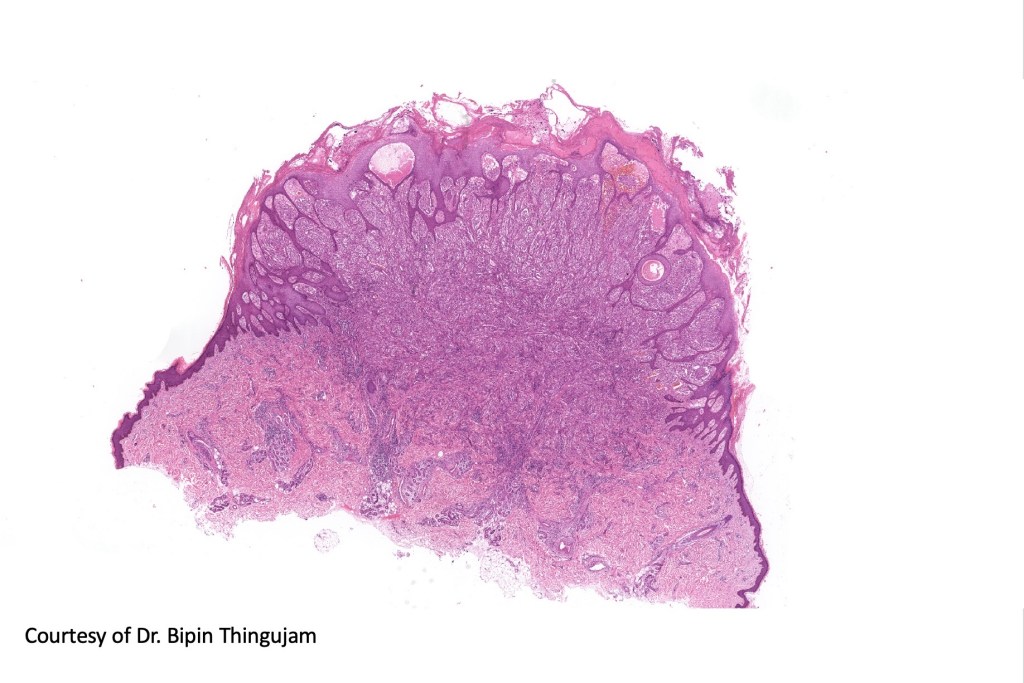

•Sharply circumscribed (begins and ends with a nest), symmetrical dome-shaped lesion. Symmetry is both horizontal and vertical (see image below)

•Wedge-shaped with the base uppermost or sometimes plaque-shaped silhouette

•Matures with depth-often best recognized at scanning/low power magnification & readily confirmed with S100 or MART1